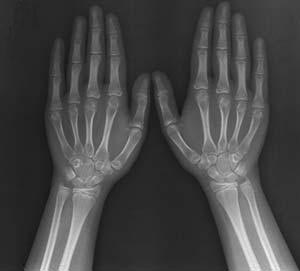

(图:冯先生 后的手指关节X光)

治疗第一个疗程后,冯先生就感觉左手中指关节疼痛减轻,肿胀开始消退,关节僵硬感有所缓解。治疗第二个疗程后,冯先生的左手中指关节肿胀基本消失,肤色未见发红,按压还有些许微痛,双膝关节酸痛感缓解,左踝关节皮温恢复正常。治疗第三个疗程后,冯先生的左踝、左手中指关节红肿僵痛全部消失,小指关节恢复正常,手指握张有力手,脚踝转动灵活。根据治疗效果,章晓辉主任还为冯先生安排了药离子渗透技术巩固治疗,根本性恢复嘌呤代谢正常状态,平衡血尿酸,达到标本兼治。

一个月的巩固治疗结束后,冯先生来院复诊,数据显示血尿酸228umol/l,肝肾功能均正常, 血压134/72mmHg,已达到临床 标准。半年后,我院医务人员对冯先生进行电话回访,得知其治疗至今没有不适症状,也没有不适的现象。